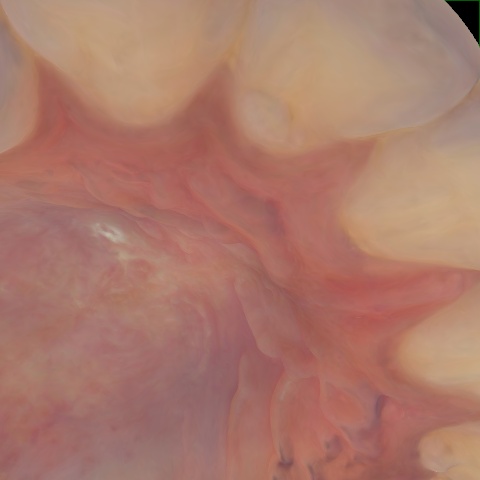

Annotated as "Good"